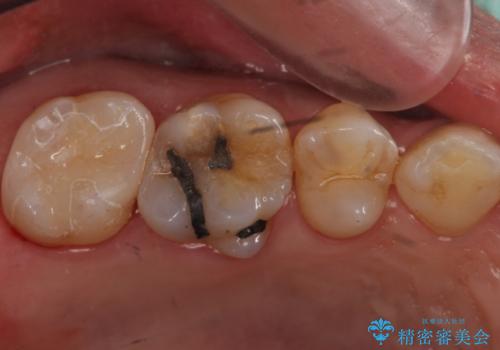

- 昔、治療された銀歯が気にな流ということを主訴で来院された患者様です。

銀歯を外し、虫歯治療を行い、セラミックインレーにて治療しました。

銀歯を除去し、虫歯をとって、セラミックインレーにて治療を行いました。